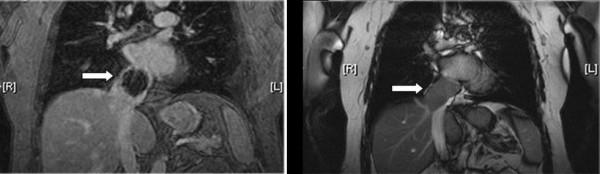

A 68-year-old white female presented with two years of progressively worsening dyspnea. Echocardiography revealed a large right atrial mass and partial obstruction of the inferior vena cava. Further imaging revealed a cystic dense mass in the inferior vena cava and right atrium. Immunohistochemical stains were consistent with leiomyosarcoma. Intraoperatively, the tumor was noted to originate from the posterior aspect of the inferior vena cava. The patient underwent successful resection of the mass. Adjuvant radiation therapy was completed. The patient's dyspnea gradually improved and she continues to remain disease free five years post-resection.

摘要